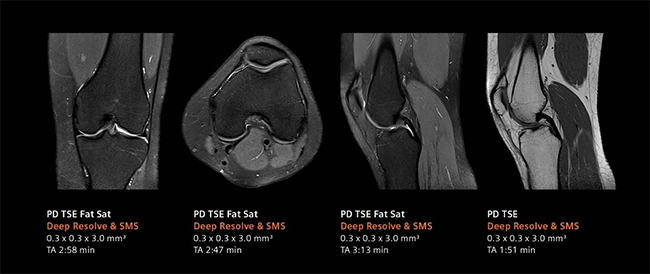

デジタル化により高画質と撮像時間の短縮を実現するべく,画像再構成にAI技術を用いて開発されたのがDeep Resolve(ディープ・レゾルブ)。

Deep Resolveは,ディープラーニング(深層学習)とターゲットデノイジング(ノイズの標的除去)により画像のノイズ除去や撮像した画像を高分解能化することで,高品質な画像の取得と撮影時間の短縮*1を可能にする。検査精度やワークフローの向上のほか,被検者の快適性や質の高い医療へのアクセス向上が期待される。

左:ルーチン検査画像, 右:Deep Resolveによる再構成画像

整形領域のルーチン検査画像(合計検査時間:10:49 min)